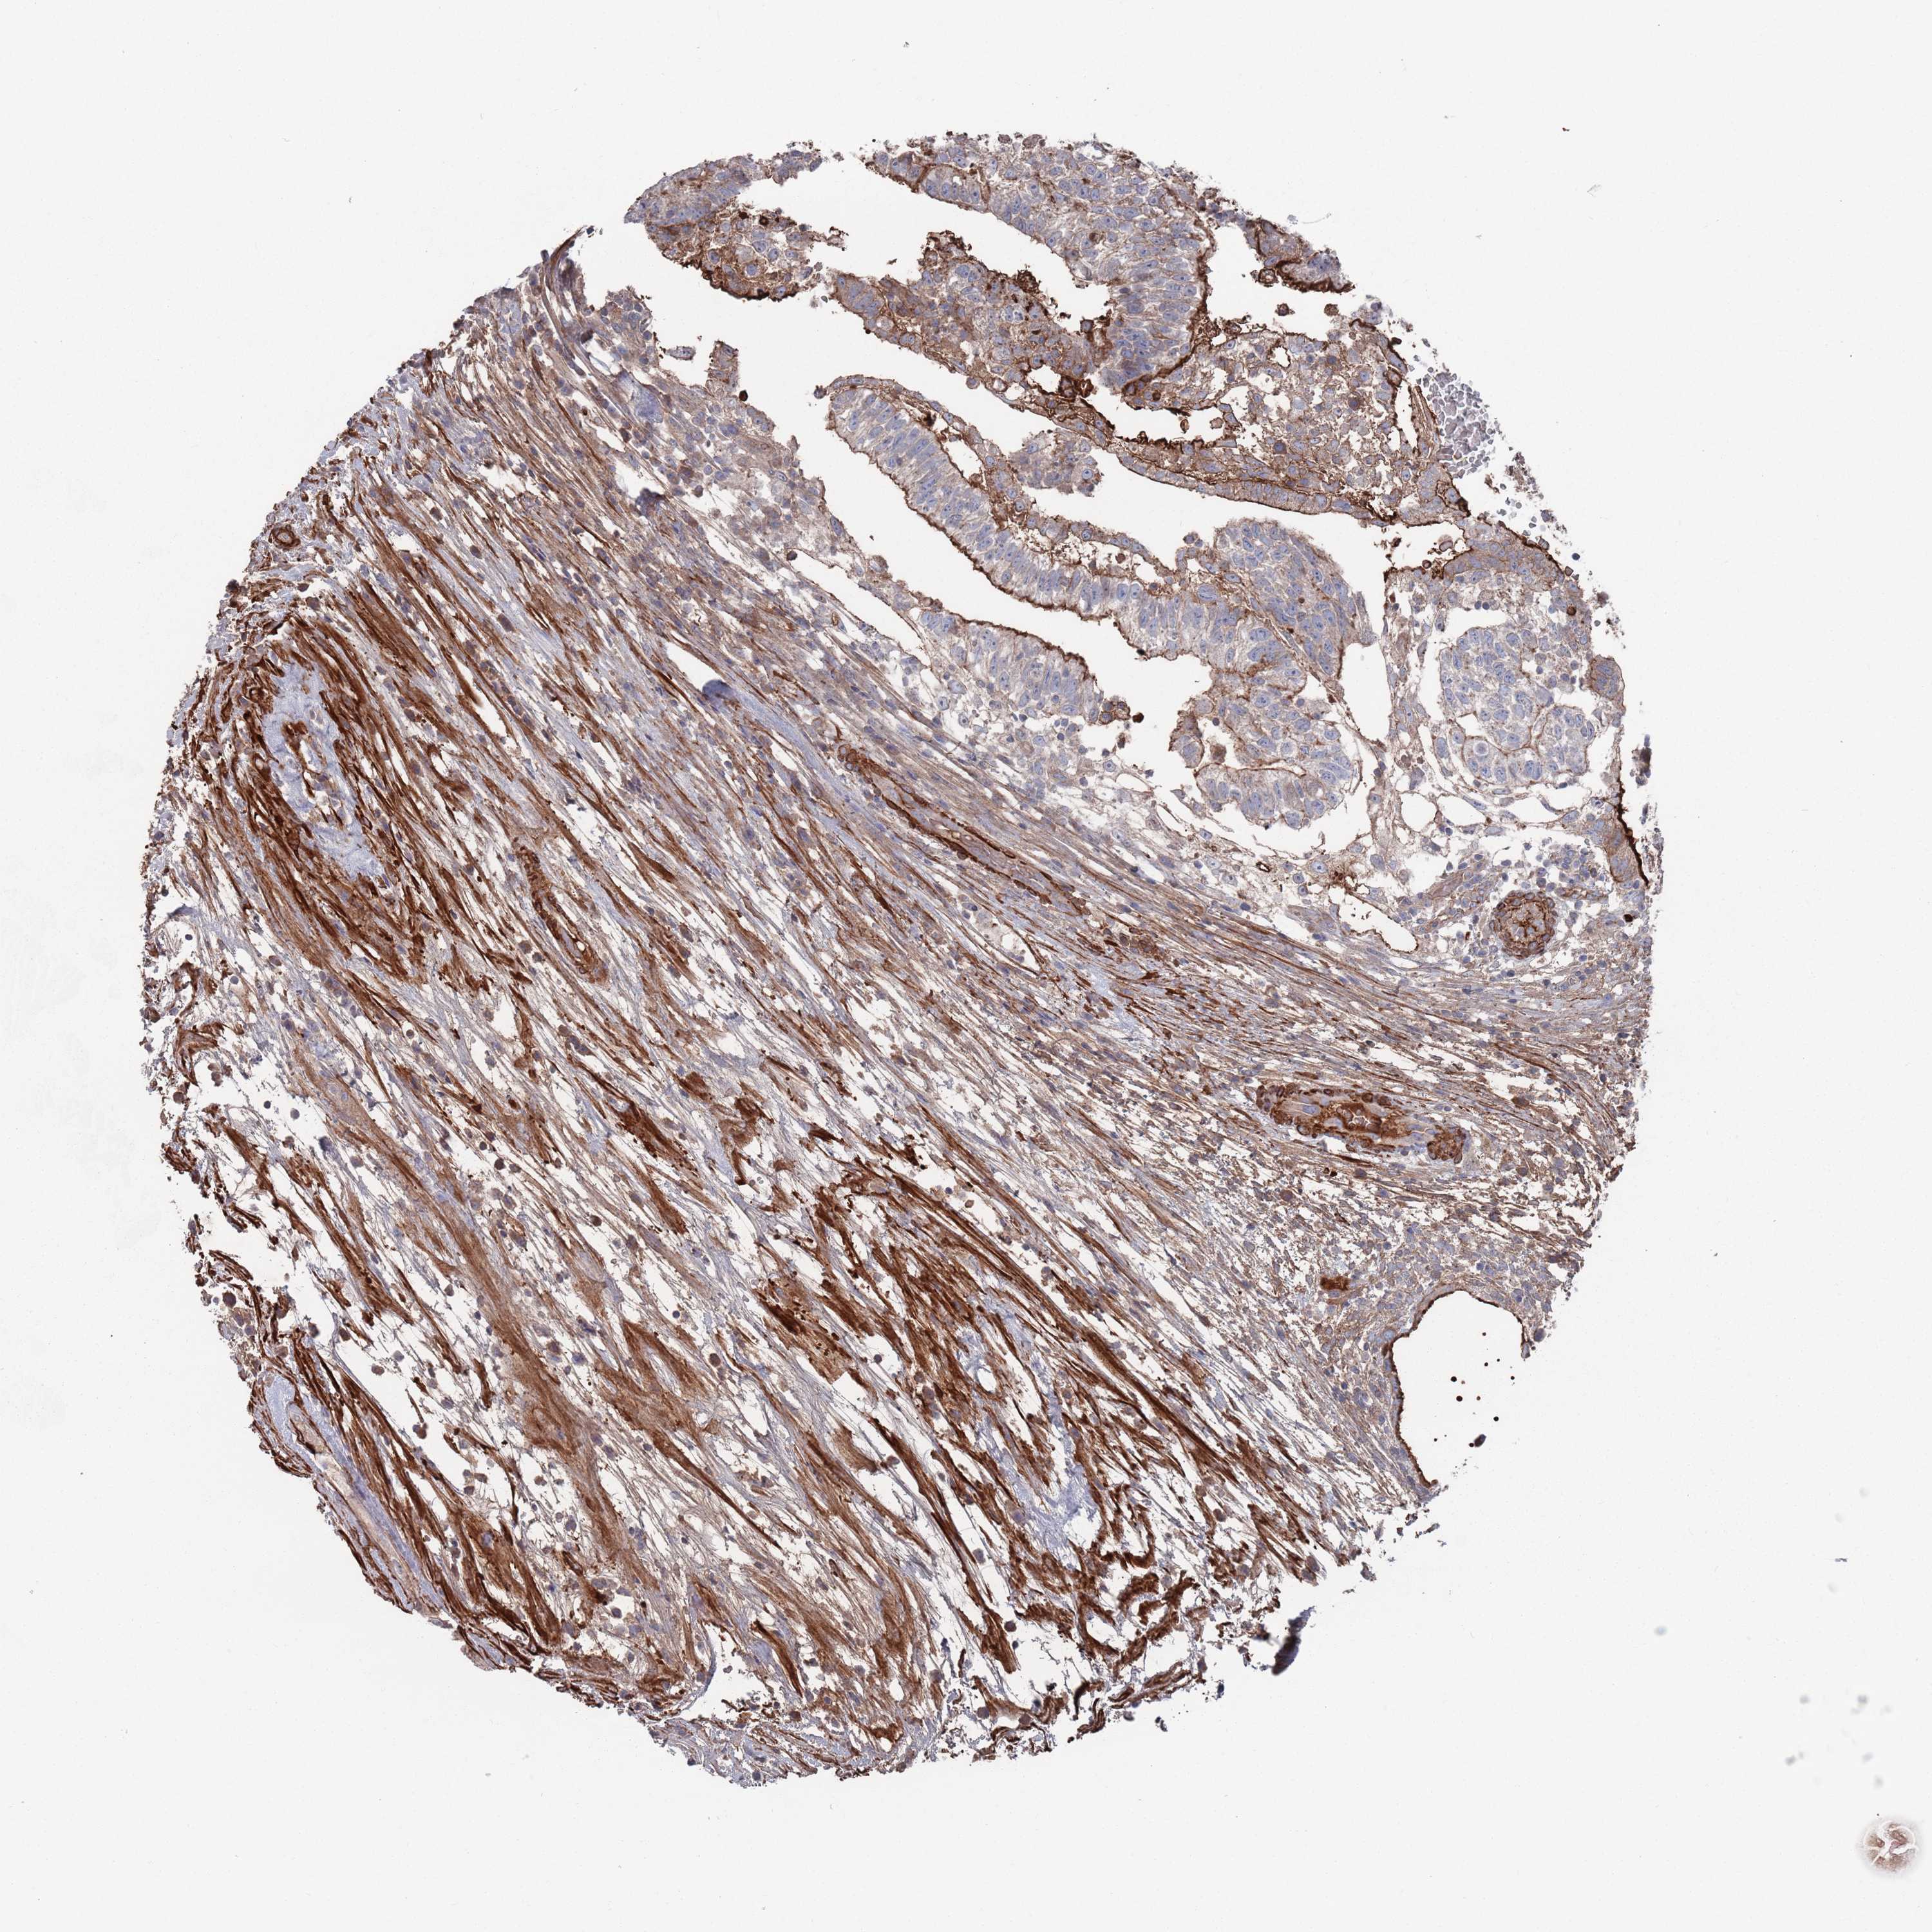

TESTIS CANCER - Protein expressioni

A mouse-over function shows sample information and annotation data. Click on an image to view it in a full screen mode. Samples can be filtered based on level of antibody staining by selecting one or several of the following categories: high, medium, low and not detected. The assay and annotation is described here.

Note that samples used for immunohistochemistry by the Human Protein Atlas do not correspond to samples in the TCGA dataset.

Antibody stainingi

Antibody staining in the annotated cell types in the current human tissue is reported as not detected, low, medium, or high, based on conventional immunohistochemistry profiling in selected tissues. This score is based on the combination of the staining intensity and fraction of stained cells.

Each image is clickable and will lead to virtual microscopy that enables deeper exploration of all samples and also displays staining intensity scores, fraction scores and subcellular localization as well as patient and tissue information for each sample.

Antibody HPA042978

Antibody HPA048473

Staining

High

Medium

Low

Not detected

Intensity

Strong

Moderate

Weak

Negative

Quantity

>75%

75%-25%

<25%

None

Location

Nuclear

Cytoplasmic/membranous

Cytoplasmic/membranous,nuclear

Carcinoma, Embryonal, NOS

Seminoma, NOS